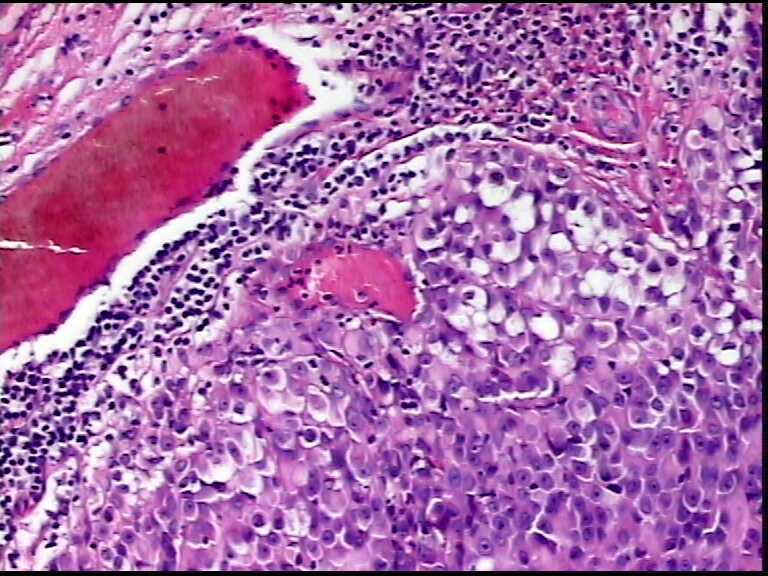

患者男性,34岁,临床没给提供,该患者梅毒阳性

• 请各位老师会诊一下 颌下淋巴结图1

图1

颌下淋巴结肿大,送检肿物直径2.5cm,切面灰粉色,质地嫩,先做了个LCA瘤细胞阴性

形态符合霍奇金淋巴瘤(看到比较典型的R-S细胞)。

淋巴结内见大量宽而嗜酸性胞浆的肿瘤细胞,瘤细胞核大,偏心分布,核仁明显,成上皮样表现,部分似有腺泡样排列,符合淋巴结转移性恶性肿瘤,首先除外转移癌,恶性黑色素瘤,继而除外浆细胞瘤(岁数不太符合),横纹肌肿瘤等。

淋巴结内见大量宽而嗜酸性胞浆的肿瘤细胞,瘤细胞核大,偏心分布,核仁明显,成上皮样表现,部分似有腺泡样排列,符合淋巴结转移性恶性肿瘤,首先除外转移癌,恶性黑色素瘤,继而除外浆细胞瘤(岁数不太符合),横纹肌肿瘤等。同意楼上的观点。